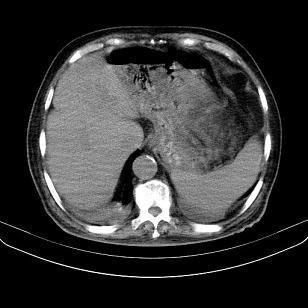

标题: CT21671:男,88岁,左上腹包块 [打印本页]

标题: CT21671:男,88岁,左上腹包块

患者因咳嗽而住院,自觉右上腹包块,无其他不适。